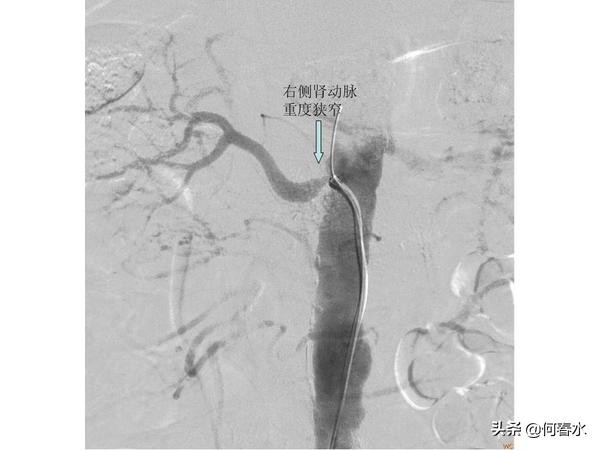

患者至今随访5年,支架通畅,头晕等脑缺血症状完全消失。但是春节后再次出现头晕不适,在职工医院检查发现右侧颈动脉重度狭窄,右侧颅内梗塞病灶,左侧颅内未有梗塞病灶。入住我科后,造影检查发现:右侧颈动脉重度狭窄伴有溃疡形成,左侧颈动脉支架通畅,右侧肾动脉重度狭窄。

右侧颈动脉重度狭窄且伴有溃疡,若采用保护伞类远端保护装置极有可能在通过保护伞的时候将狭窄处的血栓或斑块碰落引起脑梗塞,所以我们采用最先进的近端保护装置—MOMA阻断球囊技术,有效提高了手术的安全性。